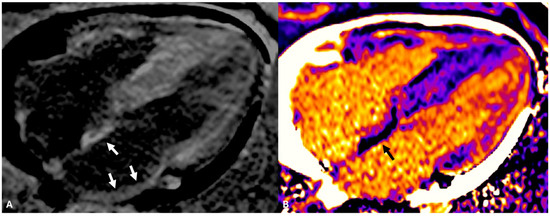

- Oakes, R.S.; Badger, T.J.; Kholmovski, E.G.; Akoum, N.; Burgon, N.S.; Fish, E.N.; Blauer, J.J.; Rao, S.N.; DiBella, E.V.; Segerson, N.M.; et al. Detection and quantification of left atrial structural remodeling with delayed-enhancement magnetic resonance imaging in patients with atrial fibrillation. Circulation 2009, 119, 1758–1767. [Google Scholar] [PubMed]

- Benito, E.M.; Carlosena-Remirez, A.; Guasch, E.; Prat-González, S.; Perea, R.J.; Figueras, R.; Borràs, R.; Andreu, D.; Arbelo, E.; Tolosana, J.M.; et al. Left atrial fibrosis quantification by late gadolinium-enhanced magnetic resonance: A new method to standardize the thresholds for reproducibility. Europace 2017, 19, 1272–1279. [Google Scholar] [CrossRef]

- Khurram, I.M.; Beinart, R.; Zipunnikov, V.; Dewire, J.; Yarmohammadi, H.; Sasaki, T.; Spragg, D.D.; Marine, J.E.; Berger, R.D.; Halperin, H.R.; et al. Magnetic resonance image intensity ratio, a normalized measure to enable interpatient comparability of left atrial fibrosis. Heart Rhythm 2014, 11, 85–92. [Google Scholar] [CrossRef]